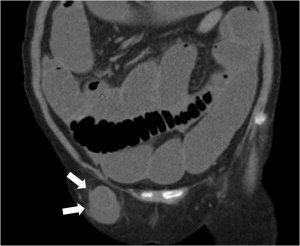

Å»ÀåÀº ¸ö ¾ÈÀÇ Àå±âµéÀ» º¸È£Çϰí ÀÖ´Â º¹º® µîÀÇ ±â°üÀÌ ¾àÇØÁ® ¸ö ¾ÈÀÇ Àå±â°¡ ¸ö ¹ÛÀ¸·Î µ¹ÃâµÇ´Â Çö»óÀ» ¸»ÇÑ´Ù. º¹º® Å»ÀåÀº º¹°­À» µÑ·¯½Ñ ±ÙÀ°°ú ±Ù¸· »çÀÌ¿¡ º¹¸·ÀÌ ÁÖ¸Ó´Ï ¸ð¾çÀ¸·Î µ¹ÃâµÇ¾î ºñÁ¤»óÀûÀÎ ÇüŸ¦ ÀÌ·ç´Â »óÅÂÀÌ´Ù.

ÁÖ¸Ó´Ï ¼Ó¿¡ º¹°­ ³» Àå±â°¡ Æ÷ÇԵDZ⵵ ÇÑ´Ù. Å»ÀåÀº »ý±ä ºÎÀ§¿¡ µû¶ó ¿©·¯ °¡Áö·Î ºÐ·ùµÇ´Âµ¥ °¡Àå ÈçÇÑ ÇüŰ¡ »çŸ±¸´Ï ºÎÀ§¿¡ »ý±â´Â ¼­ÇýºÎ Å»ÀåÀÌ°í ±× ¿Ü¿¡ ´ëÅð¿Í ¾Æ·§¹è°¡ ¸¸³ª´Â ºÎÀ§¿¡ »ý±â´Â ´ëÅð Å»Àå, ¼ö¼ú »óó ºÎÀ§¿¡ »ý±â´Â ¹ÝÈç Å»Àå, ¹è²Å ºÎÀ§ÀÇ ¾àÇØÁø ºÎºÐÀ» ÅëÇØ ¹ß»ýÇÏ´Â Á¦´ë Å»Àå µîÀÌ ÀÖ´Ù.